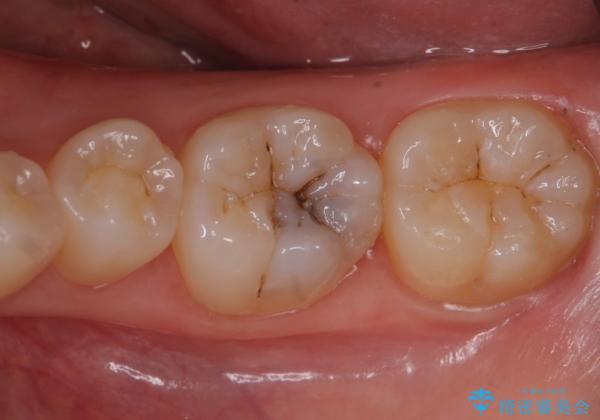

歯が黒いのが気になる

- 奥歯が黒いのが気になるとのことで来院。

レントゲンを確認したところ虫歯が大きくないので、以下の治療の提案を行った。

レジンの樹脂は安価で1日で治療を終える事ができるが

吸水性があり、どんなに丁寧に磨いていても劣化してきてしまいます。

また、歯と歯質の隙間ができてしまい、虫歯の再発リスクが高まります。